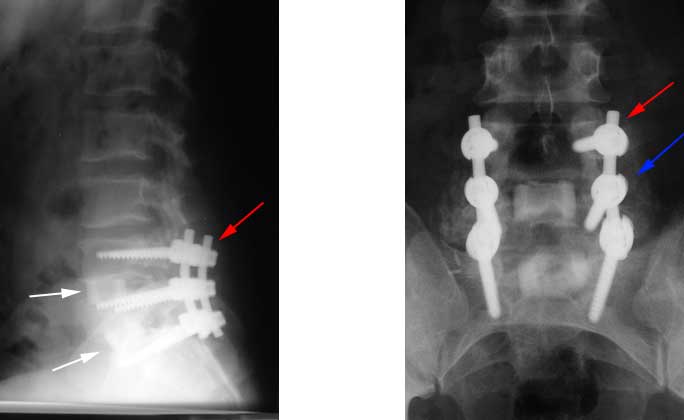

At times, a combination of a front and back approach is used for obtaining a fusion. The figure below shows cadaver bone graft placed from the abdomen [marked by white arrows on the left image] with screws and rods placed from the back side of the patient [marked by the blue and red arrows].